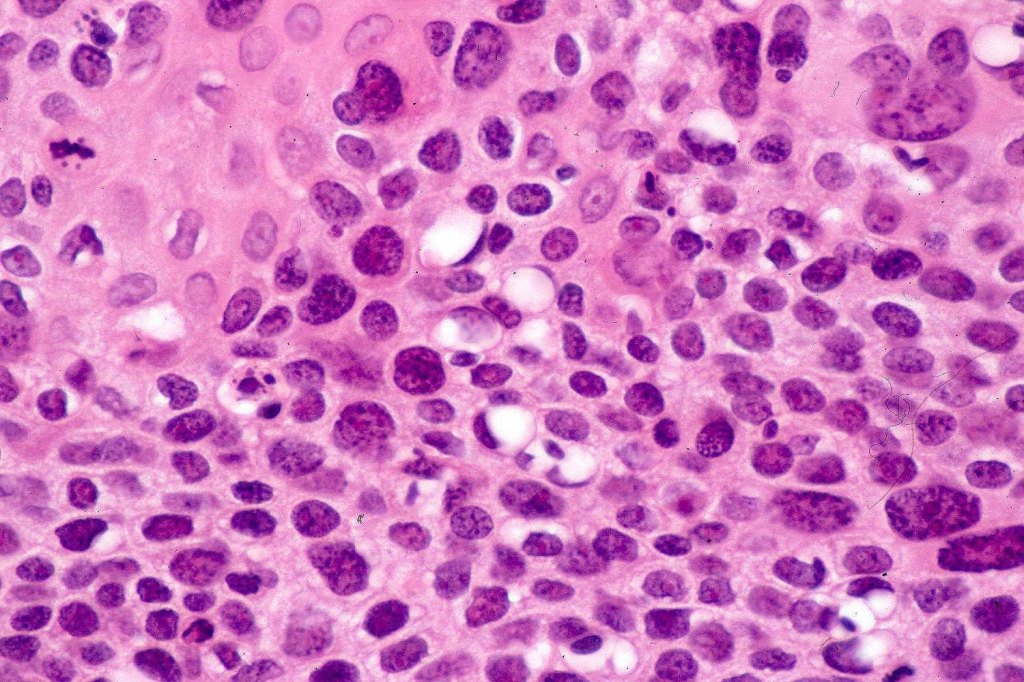

•Variable nuclear pleomorphism

•Some tumors are deceptively bland & diagnosis depends upon growth pattern or is made in retrospect after metastasis

•Mitoses often conspicuous and sometimes abnormal

•Variable necrosis (may be comedo-like)